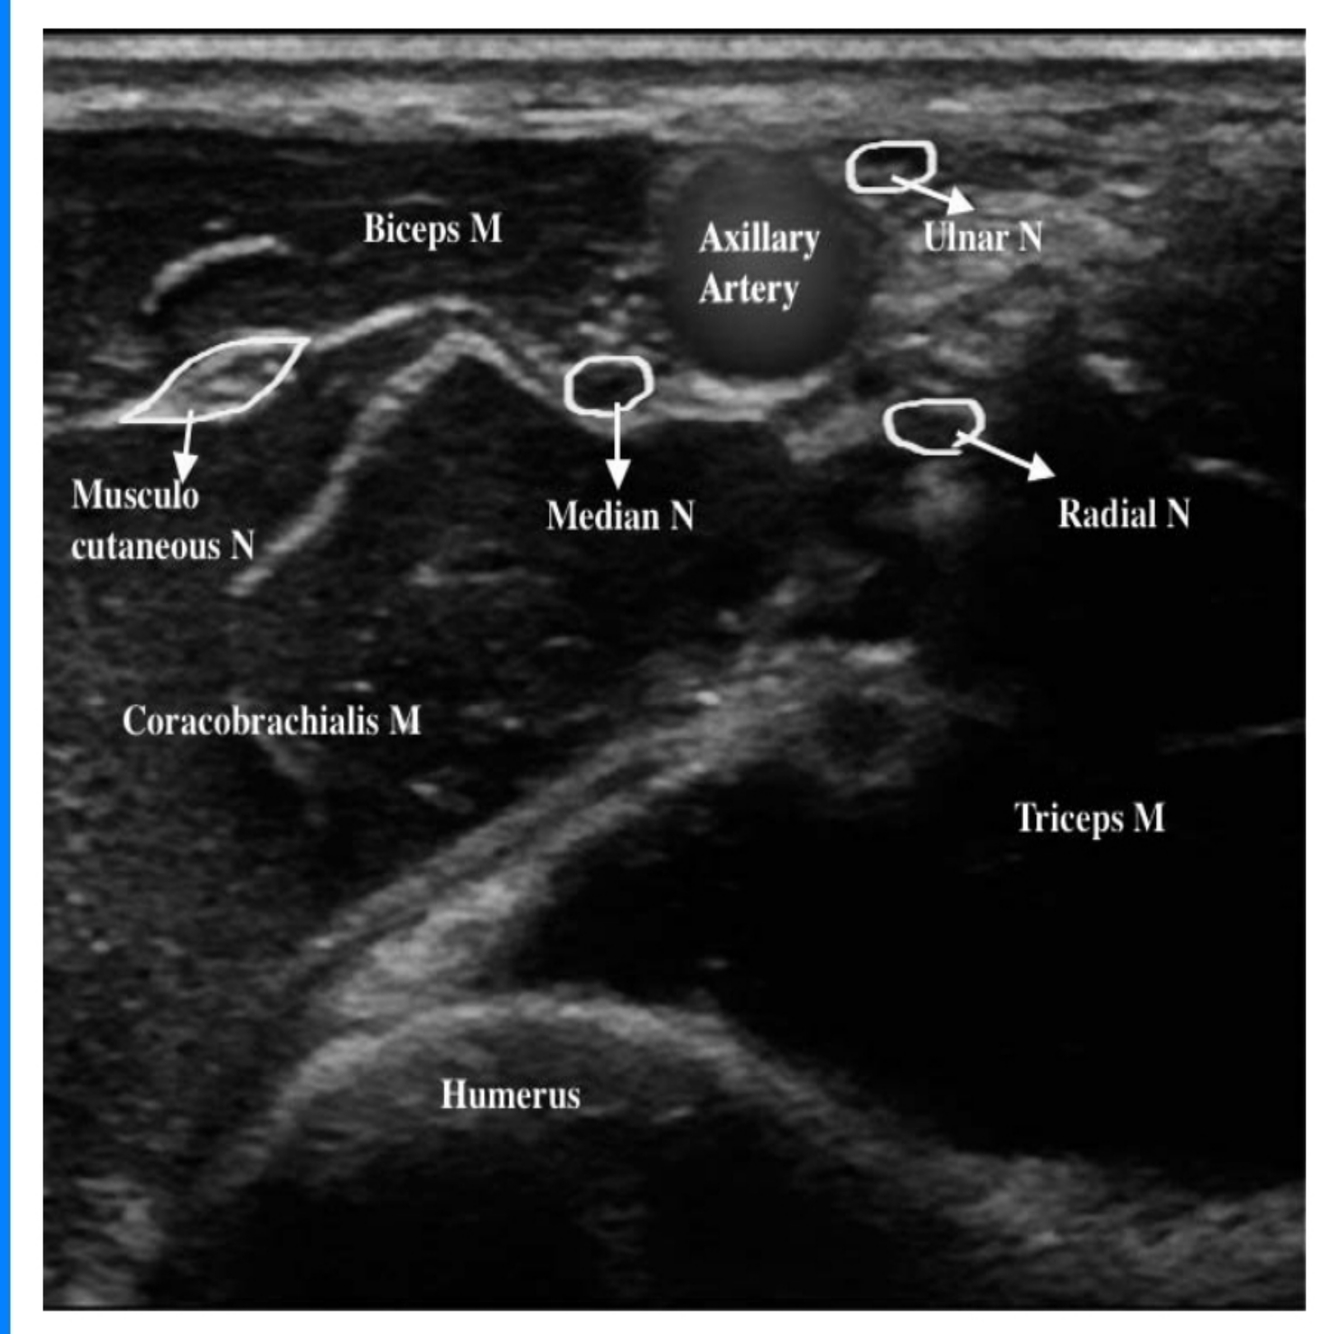

Look at the ultrasound image in Figure 3.1a and name the structures.

A

○ Median, ulnar, and radial nerves are seen scattered around the axillary artery with the tissue sheath.

○ The musculocutaneous nerve is seen between the biceps and coracobrachialis away from the rest of the brachial plexus.

○ The axillary vein is compressed leading to the possibility of accidental intravascular injection of local anaesthetic

• Ultrasound probe positioned with short axis to arm just distal to pectoralis major insertion

• Aim to achieve local anaesthetic spread around the axillary artery covering median, ulnar, and radial nerve and a separate injection to cover the musculocutaneous nerve

• Total volume of local anaesthetic 20–25 mls of 0.25% L – Bupivacaine (5–7 mL around each nerve)